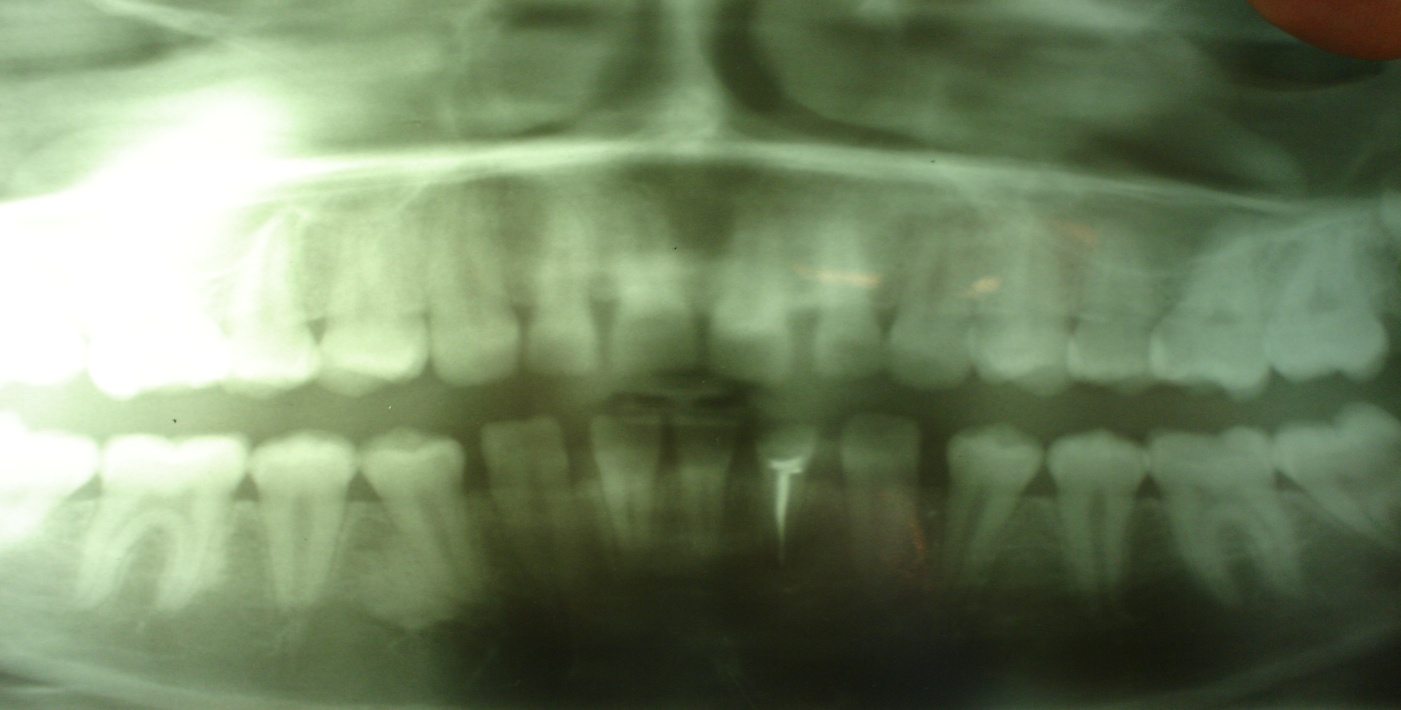

На ортопантомограмме удовлетворительного качества определяется фолликул 48-го зуба, стадия минерализации зачатка – колпачок, 47 зуб – верхушки корней не сформированы. 46 зуб – корни сформированы. Вдоль медиального корня полоска затемнения четко выраженная с фестончатыми контурами с небольшими участками просветления. 45 зуб – корень не сформирован. 44 зуб - верхушка корня сформирована. У дистальной поверхности корня определяется образование большой плотности, охватывающее 2/3 поверхности корня. На фоне плотных полей имеются участки с меньшей контрастностью. Границы новообразования фестончатые. В нижнем отделе прослеживается полоса просветления, которая отделяет его от неизмененной кости. В среднем и верхнем отделах полоса просветления отсутствует. Периодонтальная щель не прослеживается. Корни клыков, центральных и боковых зубов сформированы. 31 зуб – корневой канал запломбирован на всем протяжении. Адентия 32-го зуба. Корни 33, 34 зубов сформированы. Корень 35-го зуба не сформирован. Корень 36-го зуба сформирован. 37 зуб в стадии незакрытой верхушки. Фолликул 38-го зуба - стадия минерализации – колпачок. В боковых отделах жевательной группы зубов межзубные перегородки на уровне эмалево-цементной границы, четко выражены их вершины. Фронтальный отдел нижней челюсти – отсутствие вершин межзубных перегородок, явления остеопороза. Верхняя челюсть – верхушки 13 и 23го зубов не закрыты. Снижение высоты межзубных перегородок в области фронтальных зубов снижена, деструкция вершин и остеопороз межзубных перегородок.

|